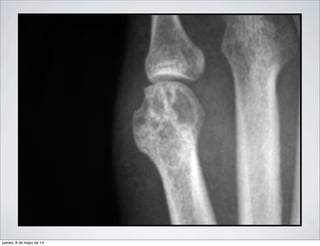

SIGNOS ASOCIADOS:

• ENGROSAMIENTO DE PARTES

BLANDAS

• DESMINERALIZACION EN BANDAS

• PINZAMIENTO DE LA INTERLINEA

ARTICULAR

•CADERA: PINZAMIENTO GLOBAL DE

LA INTERLINEA SEGUIDA DE

PROTRUSION ACETABULAR